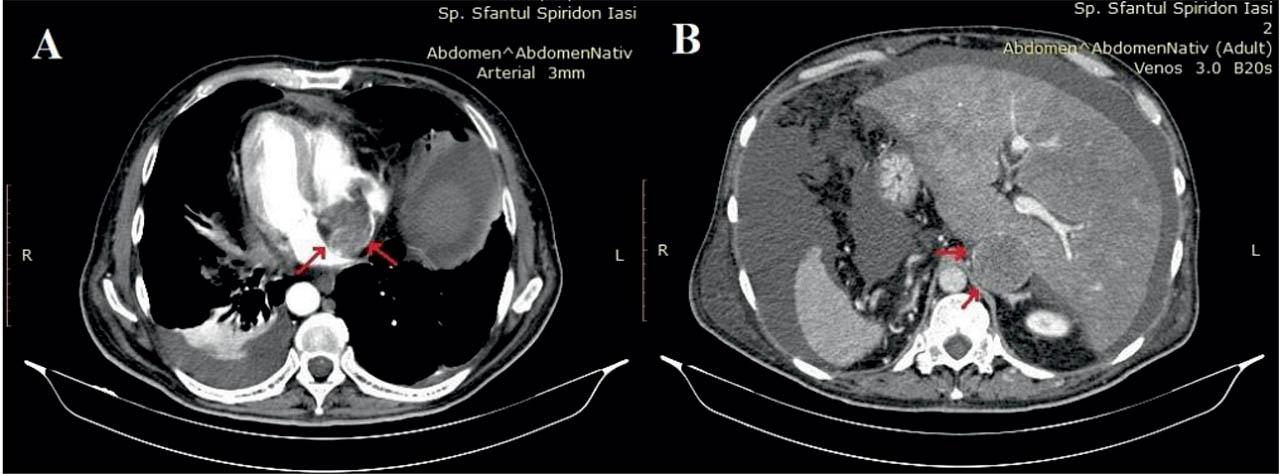

Figure 3

A. Thoracic CT arterial phase - axial view. Soft tissue mass occupying the right atrium almost completely, continued by thrombosis at the same level, with free right atrial appendage; pleural effusion. B. Abdominal CT venous phase - axial view. Filling defect of the IVC due to intraluminal non-homogeneous mass, with a diameter disproportionate larger than the aorta on the right (IVC largest diameter 53 mm); ascites.